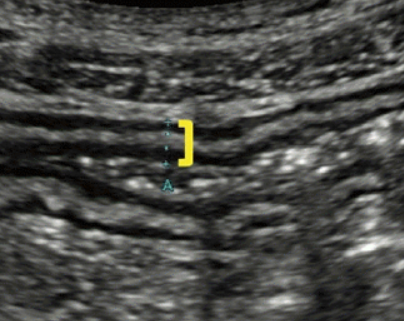

Longitudinal GI tract

Trans GI tract